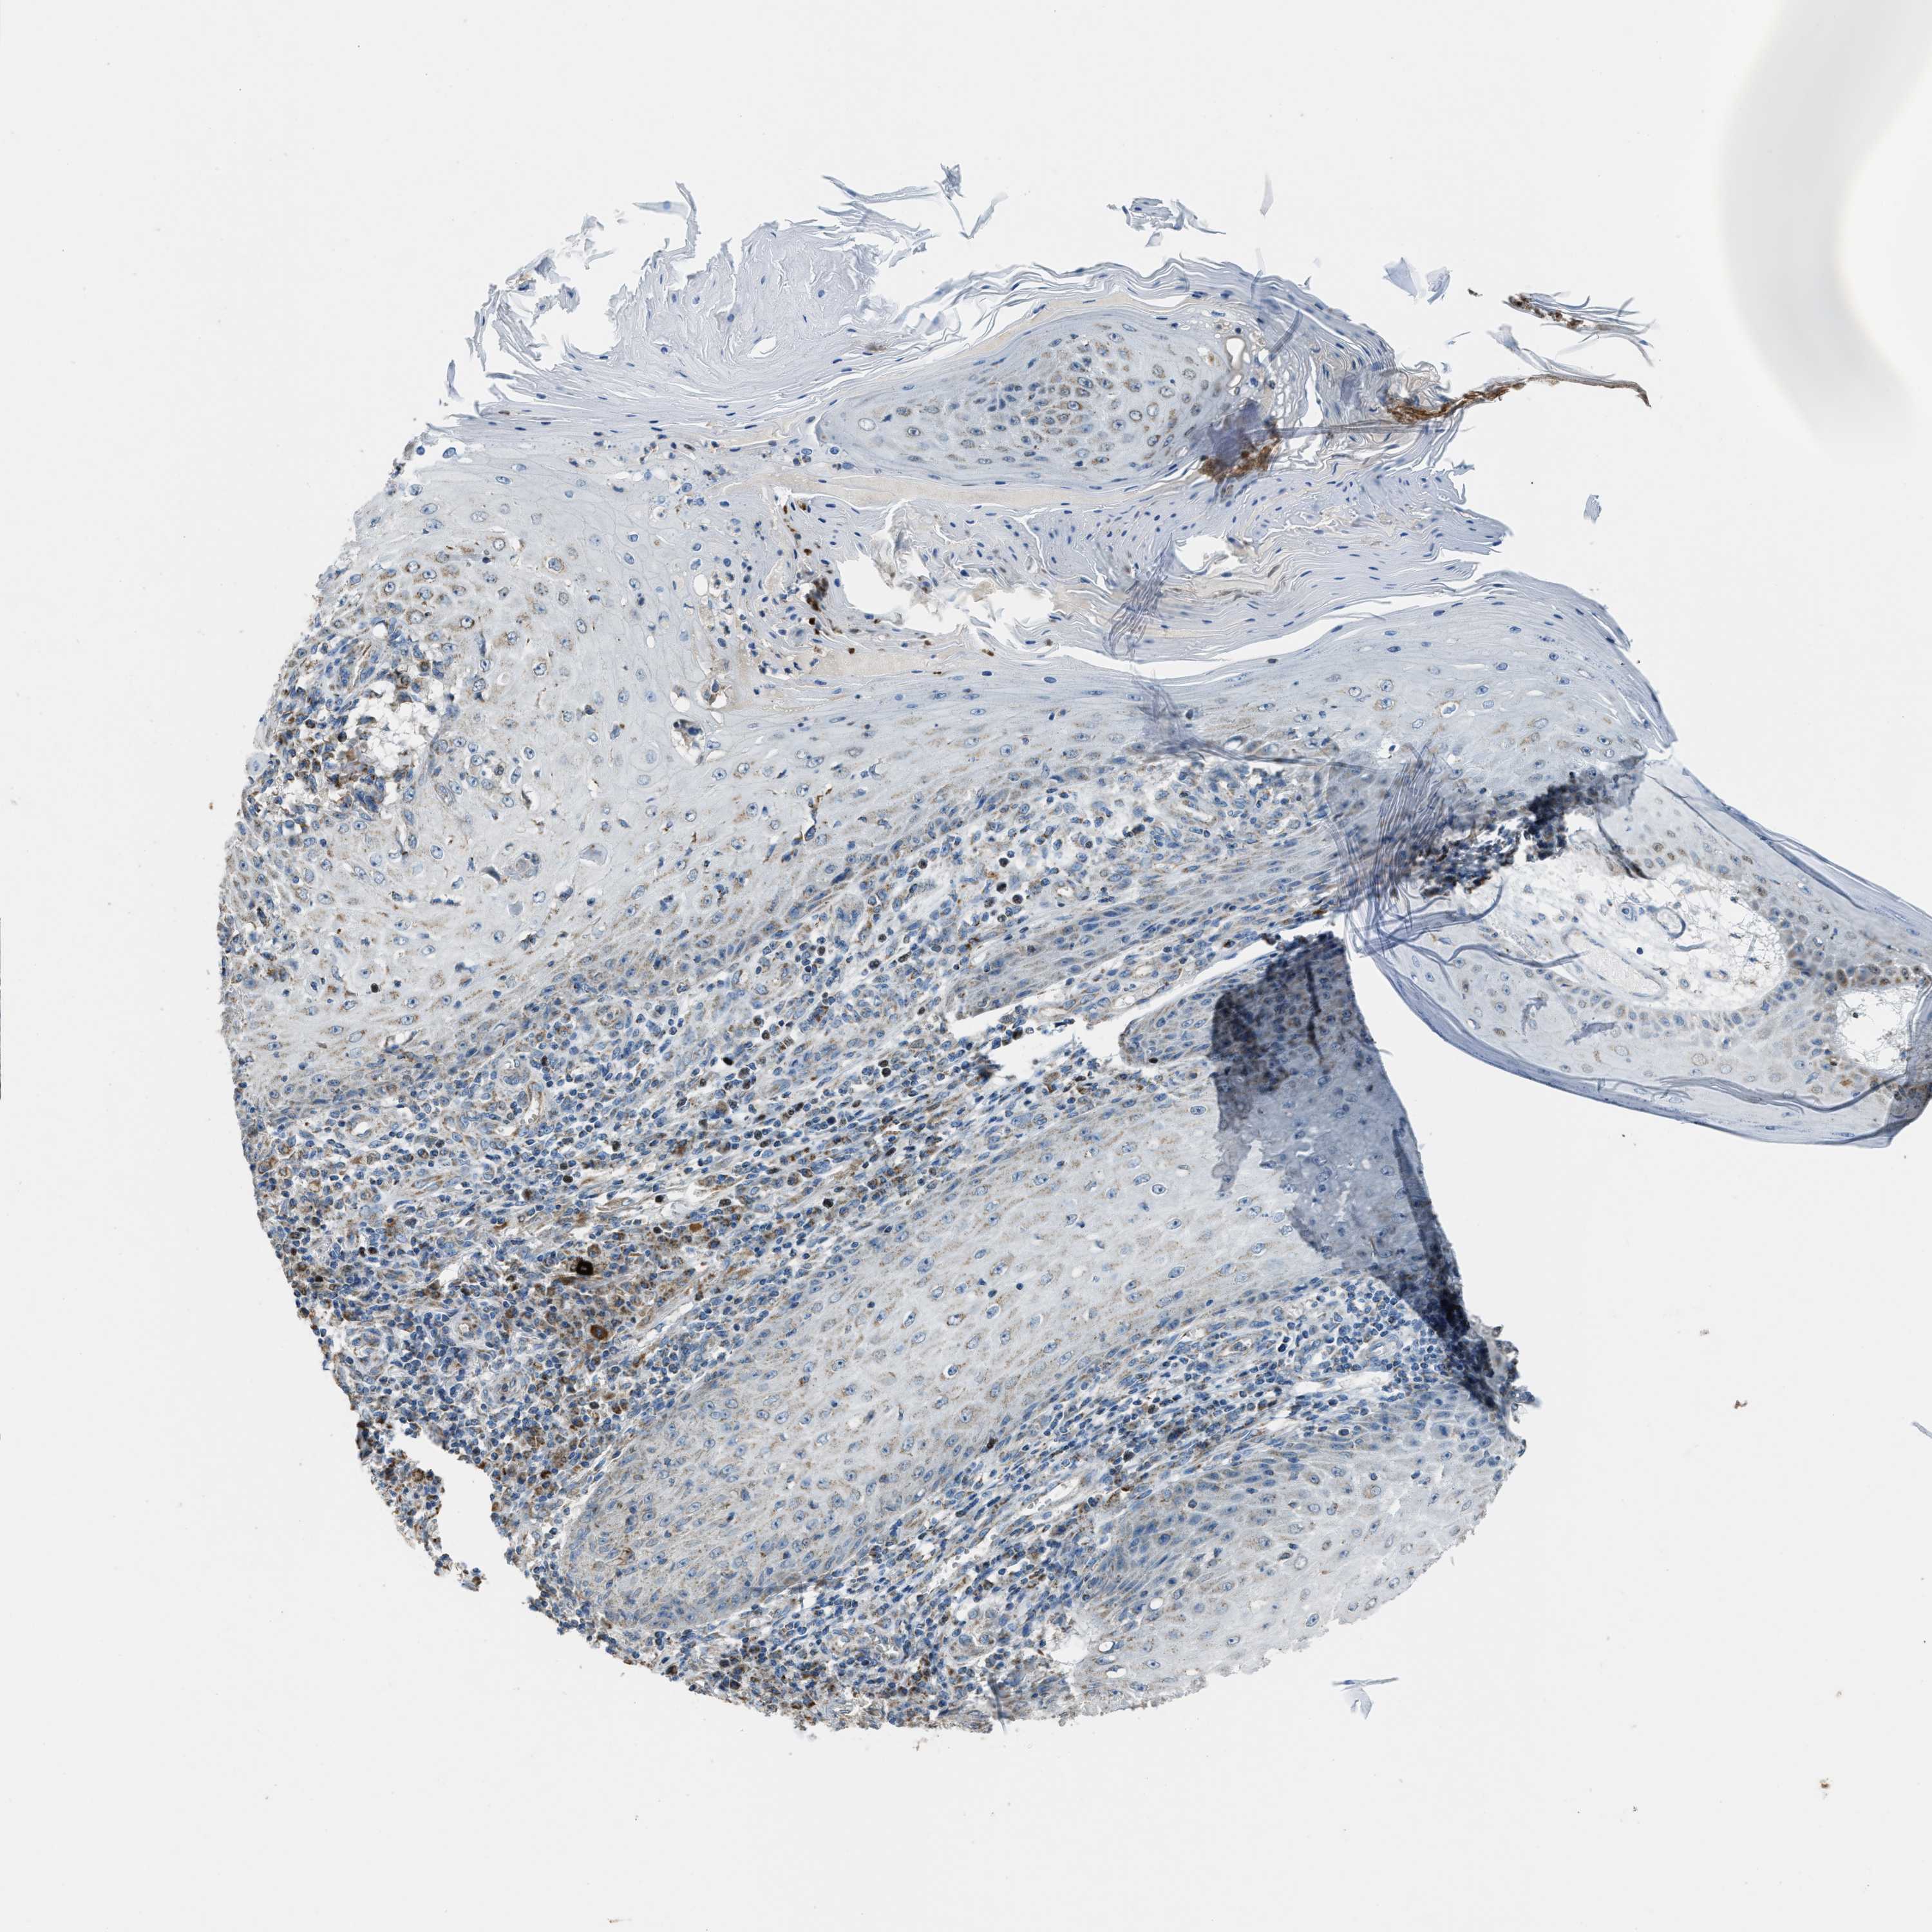

Basal cell and squamous cell cancer

SKIN CANCER - Protein expressioni

A mouse-over function shows sample information and annotation data. Click on an image to view it in a full screen mode. Samples can be filtered based on level of antibody staining by selecting one or several of the following categories: high, medium, low and not detected. The assay and annotation is described here.

Antibody stainingi

Antibody staining in the annotated cell types in the current human tissue is reported as not detected, low, medium, or high, based on conventional immunohistochemistry profiling in selected tissues. This score is based on the combination of the staining intensity and fraction of stained cells.

Each image is clickable and will lead to virtual microscopy that enables deeper exploration of all samples and also displays staining intensity scores, fraction scores and subcellular localization as well as patient and tissue information for each sample.

Antibody HPA021167

Staining

High

Medium

Low

Not detected

Intensity

Strong

Moderate

Weak

Negative

Quantity

>75%

75%-25%

<25%

None

Location

Nuclear

Cytoplasmic/membranous

Cytoplasmic/membranous,nuclear

Squamous cell carcinoma, NOS